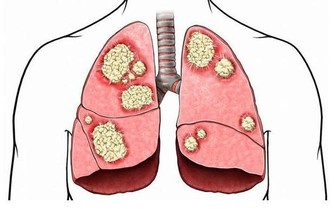

酒精對身體的危害十分廣泛包括心腦血管、中樞神經、消化系統、肝膽脾胃等,我下面著重介紹一下不大多見,與酒密切相關一種病,馬德龍病。